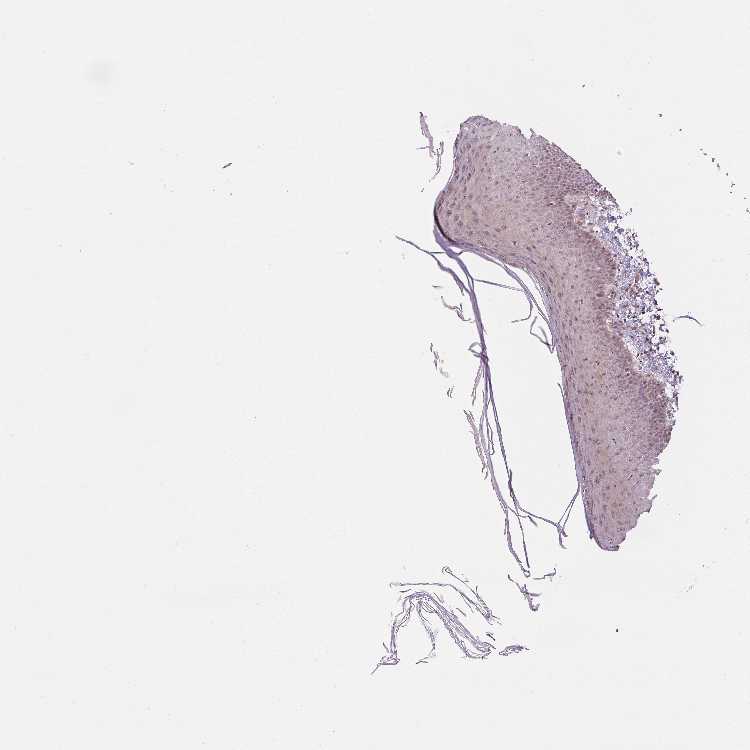

SKIN 1 - Antibody stainingi

Antibody staining in the annotated cell types in the current human tissue is reported as not detected, low, medium, or high, based on conventional immunohistochemistry profiling in selected tissues. This score is based on the combination of the staining intensity and fraction of stained cells.

Each image is clickable and will lead to virtual microscopy that enables deeper exploration of all samples and also displays staining intensity scores, fraction scores and subcellular localization as well as patient and tissue information for each sample.

Antibody HPA060452Antibody HPA062492

Langerhans LowNot detected

Fibroblasts Not detectedLow

Keratinocytes MediumNot detected

Melanocytes LowNot detected

SKIN 2 - Antibody stainingi

Epidermal cells MediumNot detected